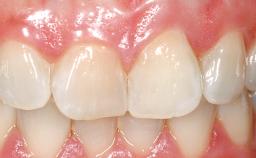

A 30-year-old female patient was referred to the office for the treatment of tooth 11. Her chief concern at the initial visit was to inquire, “Why is my tooth pink?” Upon clinical examination, it was determined that tooth 11 had a previous history of trauma and that the clinical crown had become noticeably pink in color as a result of internal resorption. This diagnosis was confirmed radiographically, indicating a large radiolucency involving the central and distal portions of the clinical crown. It was determined that restoration of this tooth was not possible, and that extraction was indicated. The presence of a mid-line diastema, which the patient wanted to reproduce, directed the treatment plan for tooth replacement utilizing a dental implant.

Mesio-Distal Space Asymmetry greater than 1 mm